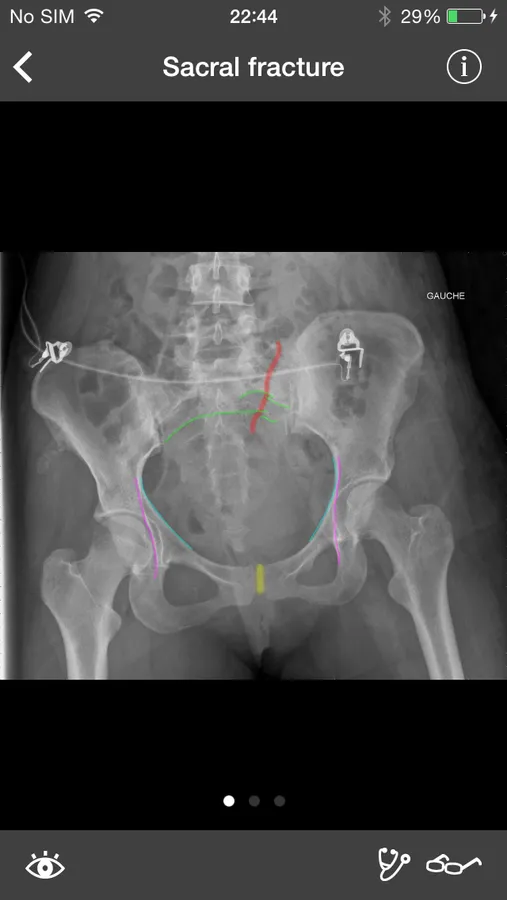

RealWorld Orthopaedics is also the best musculoskeletal radiology resource on the App Store! Not only can you see radiographs of every discussed disease, all radiologic findings can be highlighted right on the X-ray. Explore more than 150 real cases each containing:

- Clinical information regarding the patient and the mechanism of injury

- High-resolution X-rays

- All appropriate series (anteroposterior, lateral, oblique, etc.)

- Detailed radiologic interpretation

- Drawings of every radiological finding right on the X-ray

- Pre and postoperative controls